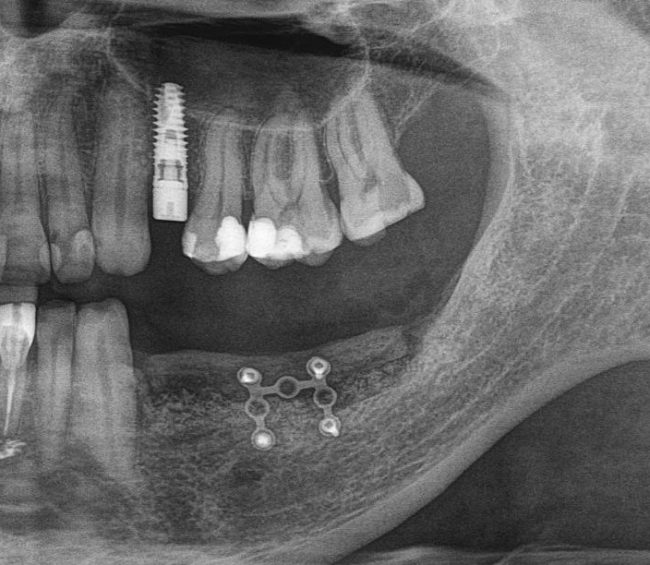

После операции:

— контрольный снимок (раньше делали ОПТГ, сейчас — строго КЛКТ)

Для этого мы сделали КЛКТ:

И КЛКТ показала нам, что с имплантатами и окружающей костью всё зашибись. Через 12 лет после операции, отсутствия наблюдения, пофигизма в замене временных коронок! Нужны ли тебе еще какие-нибудь доводы в пользу долгосрочной эффективности метода?

Серия контрольных снимков на этапах: